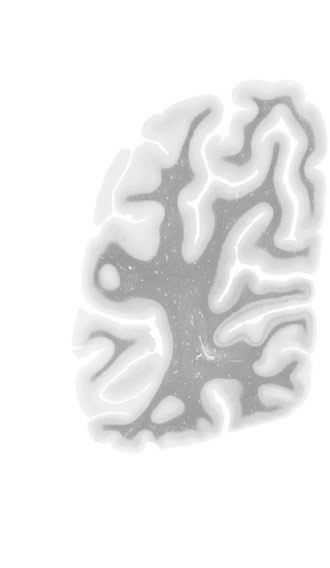

Hi-Resolution Sections · Cells (Nissl Staining) · Virtual Microscopy

Frontal sections (Nissl) from the Atlas Brain:

Macroscopy

Slice ID:

r5-0250

Plate NR:

65-66

Position:

83,8 mm